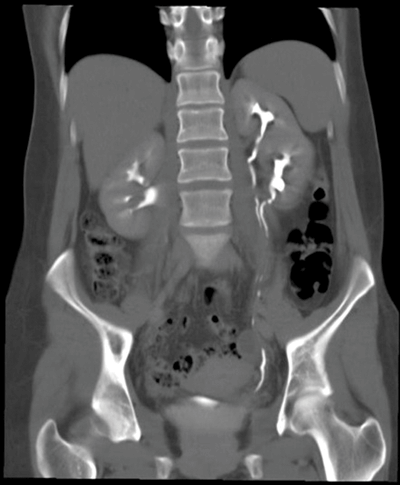

Case 3

Left duplex kidney / collecting system.

One case in 125. Incomplete - common, rarely clinically significant. Complete - rare, often clinically significant.

The Weigert-Meyer law states the upper pole moiety ureter drains infero-medial to the normal lower moiety ureter.

Ureterocoele, reflux in the lower moiety, obstruction in the upper moiety (usually due to ureterocoele), PUJ obstruction, ectopic ureters.